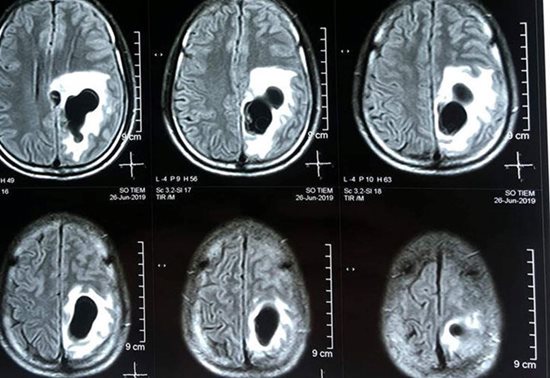

Ổ sán trong não bệnh nhân. |

Kết quả chụp CT não cho thấy có 5 ổ sán nằm rải rác trong não, trong đó có một ổ sán lớn trên đỉnh của bệnh nhân gây phù não. Bệnh nhân sau đó đã được phẫu thuật để lấy được trọn vẹn ổ nang sán khỏi não.